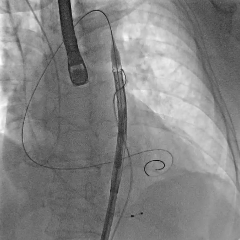

术中影像

第二次瓣膜释放

造影评估,瓣膜位置可

右侧位造影,瓣膜深度可

多角度评估,瓣膜位置可,少量瓣周漏